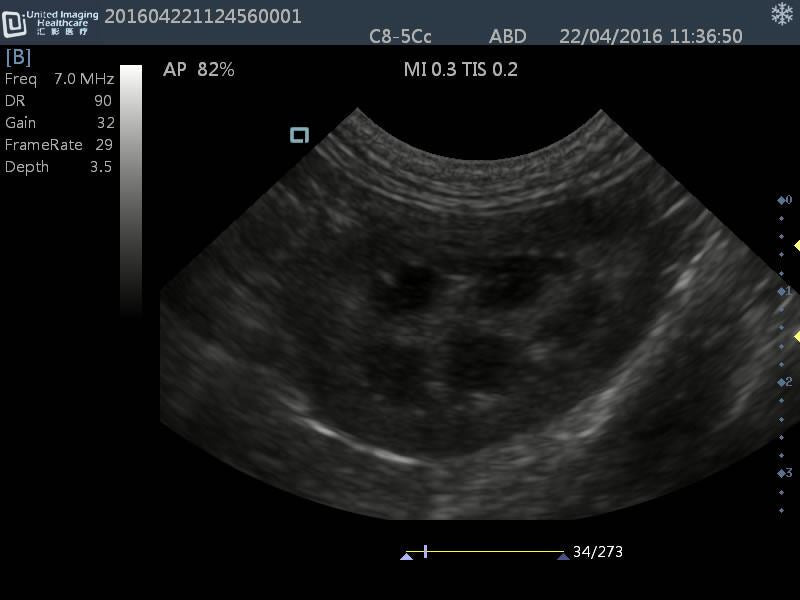

Micro-convex(R15): C8-5Cc

- Application: General small abdomen and cardiac

- Equine musculoskeletal and abdomens

- Number of element: 80

- Center frequency: 6.5MHz

- Working frequencies: 5 – 9MHz